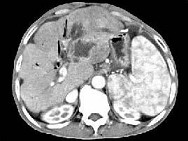

- 单项选择题根据所提供的图像,最可能的诊断是 ( )

A、肝囊肿

B、肝脓肿

C、肝胆管细胞癌伴肝硬化

D、肝细胞癌

E、以上都不是